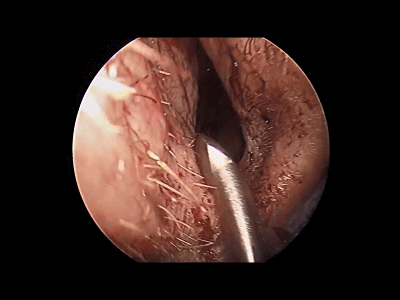

▼首先在内镜直视下逐步进入鼻腔,用吸引器吸除鼻腔内分泌物。下图示左侧鼻腔。

▼下图示右侧鼻腔。观察鼻腔、鼻甲有无黏连,鼻道有无狭窄。